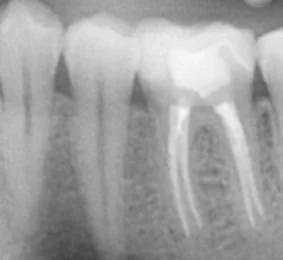

Root Canal Treatment

Root canal treatment is a procedure used to address infection or damage within the pulp (nerve) of a tooth.